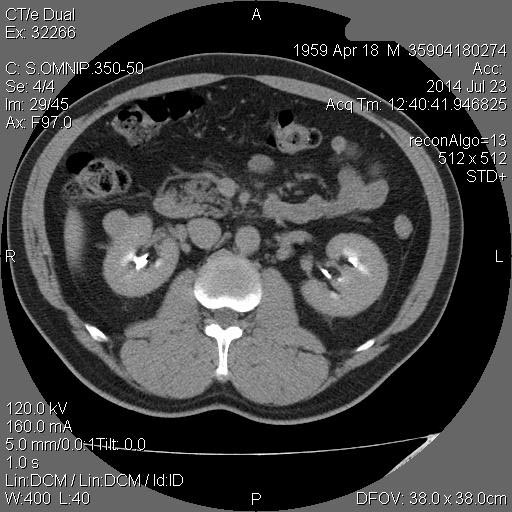

Образование в правой почке

Мужчина средних лет.Жалоб не предъявляет.

С его слов, 10 лет назад в правой почке находили кисту.

гипоэхогенное образование в среднем сегменте, деформирующее контур почки...наверное рак

Ответ каунасских радиологов - киста почки.

В том то и дело. Но тем не менее - это киста, анамнез уже несколько лет.besliu писал(а):Что-то на узи на кисту не похоже...

Динамики нет, на последнем видео четко видна киста при включенной 2й гармонике